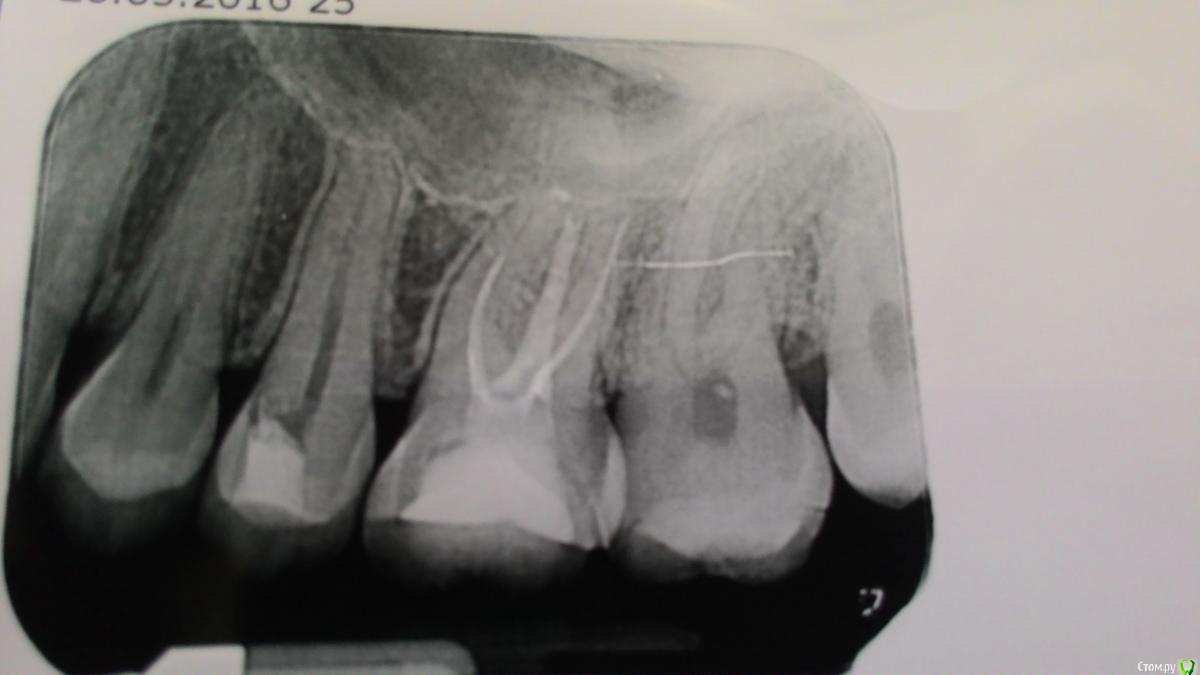

NataliaBer Опубликовано 27 мая, 2016 Автор Поделиться Опубликовано 27 мая, 2016 (изменено) Вот это вчера сделали Изменено 27 мая, 2016 пользователем NataliaBer Ссылка на комментарий

vse32 Опубликовано 27 мая, 2016 Поделиться Опубликовано 27 мая, 2016 Вот это вчера сделали В 26 серьезная недопломбировка каналов. Нужно переделывать.27 кариес медиально - лечить.25 - противоречивые мысли. Но врачу, который проводил осмотр виднее. 2 Ссылка на комментарий